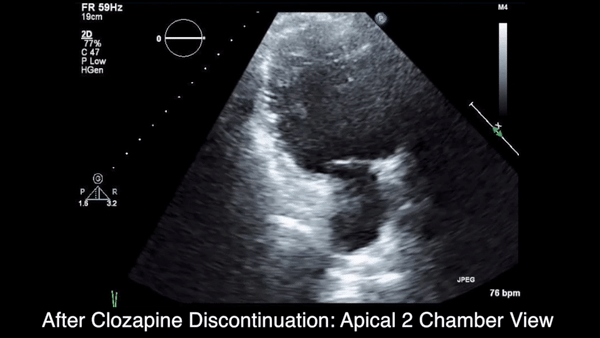

More than 4 years after the initiation of clozapine and after various treatments for multiple symptoms (Sidebar), the patient was diagnosed with heart failure (HF) with a reduced ejection fraction (EF) of 10% to 15%. She was referred to the cardiology HF clinic. Her dose of clozapine 150 mg at bedtime was discontinued after a discussion with psychiatry. She had a negative workup for other HF etiologies and was started on HF medications that included carvedilol, losartan, and spironolactone. After discontinuation of clozapine, her psychiatric symptoms worsened, and she was admitted to the psychiatry unit twice within a year. Two months after clozapine was discontinued, a repeat echocardiogram (ECHO) was obtained and was essentially unchanged. A chest X-ray (CXR) obtained 4 months after clozapine discontinuation demonstrated a normalized cardio-mediastinal silhouette. A third ECHO was ordered during her second psychiatric admission, which was 11 months after clozapine discontinuation; this revealed an improved left ventricular EF (LVEF) of 30% to 35% and resolution of left ventricular (LV) dilation.

This patient’s clinical course led to an extensive chart review that investigated whether there may have been earlier signs and symptoms of HF or cardiomyopathy. It was discovered that the initial HF signs and symptoms were likely present for about 1 year before the diagnosis was made and after having been on clozapine for about 40 months (Patient’s ECHO before and after clozapine discontinuation, click here for additional ECHO perspectives ).

It is interesting that a repeat ECHO within 2 months of clozapine discontinuation did not show an improvement, whereas a CXR at 4 months showed a normal cardiac silhouette, and an ECHO at 11 months showed an improvement in EF and normalization of LV size while on appropriate HF medications. It would have been interesting if an ECHO had been completed at 4 months to correspond with the time when the CXR normalized.